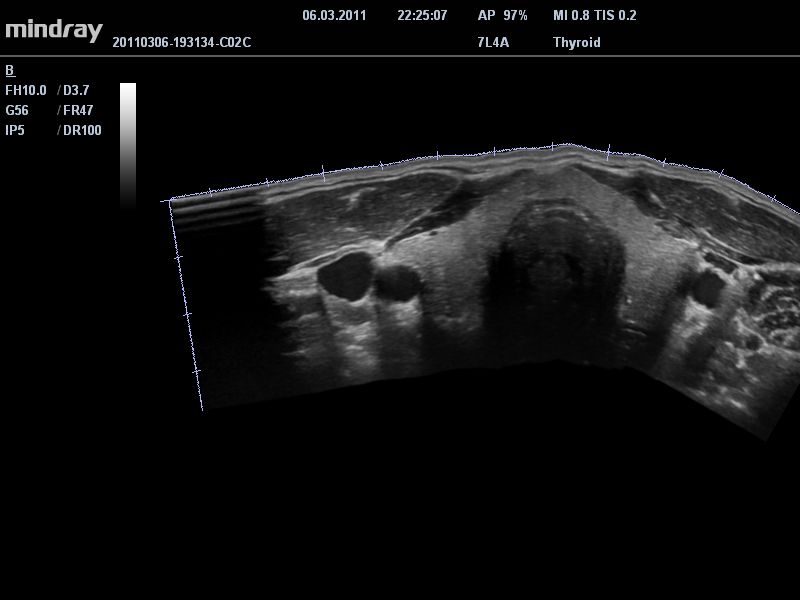

Mindray DC-T6

Ультразвуковая система Mindray DC-T6 – это инновационный аппарат для проведения высокого уровня диагностики с качественной визуализацией и широким спектром применения. Платформа рекомендована для использования в коммерчески многопрофильных медицинских учреждениях и государственных лечебных клиниках.

• Линейный ультразвуковой датчик Mindray 7L4A

• Режимы сканирования: B/M/CFM/PDI/Направленный PDI/PW, HPRF, Тканевая гармоника, М- и цветной М-режим.